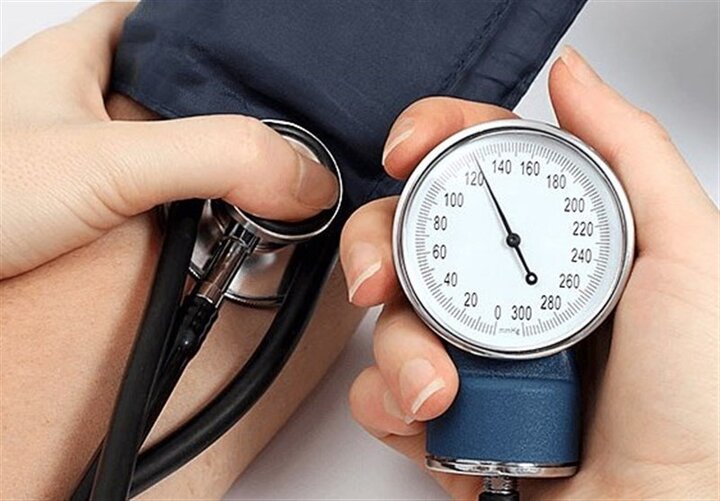

بزرگترین اشتباه بیماران مبتلا به فشارخون بالا

پرفشاری خون عامل خاموش سکته های قلبی و مغزی

متخصص بیماری های قلب و عروق و عضو پیوسته فرهنگستان علوم پزشکی ایران، از فشارخون بالا به عنوان عامل خاموش سکته های قلبی و مغزی نام برد.